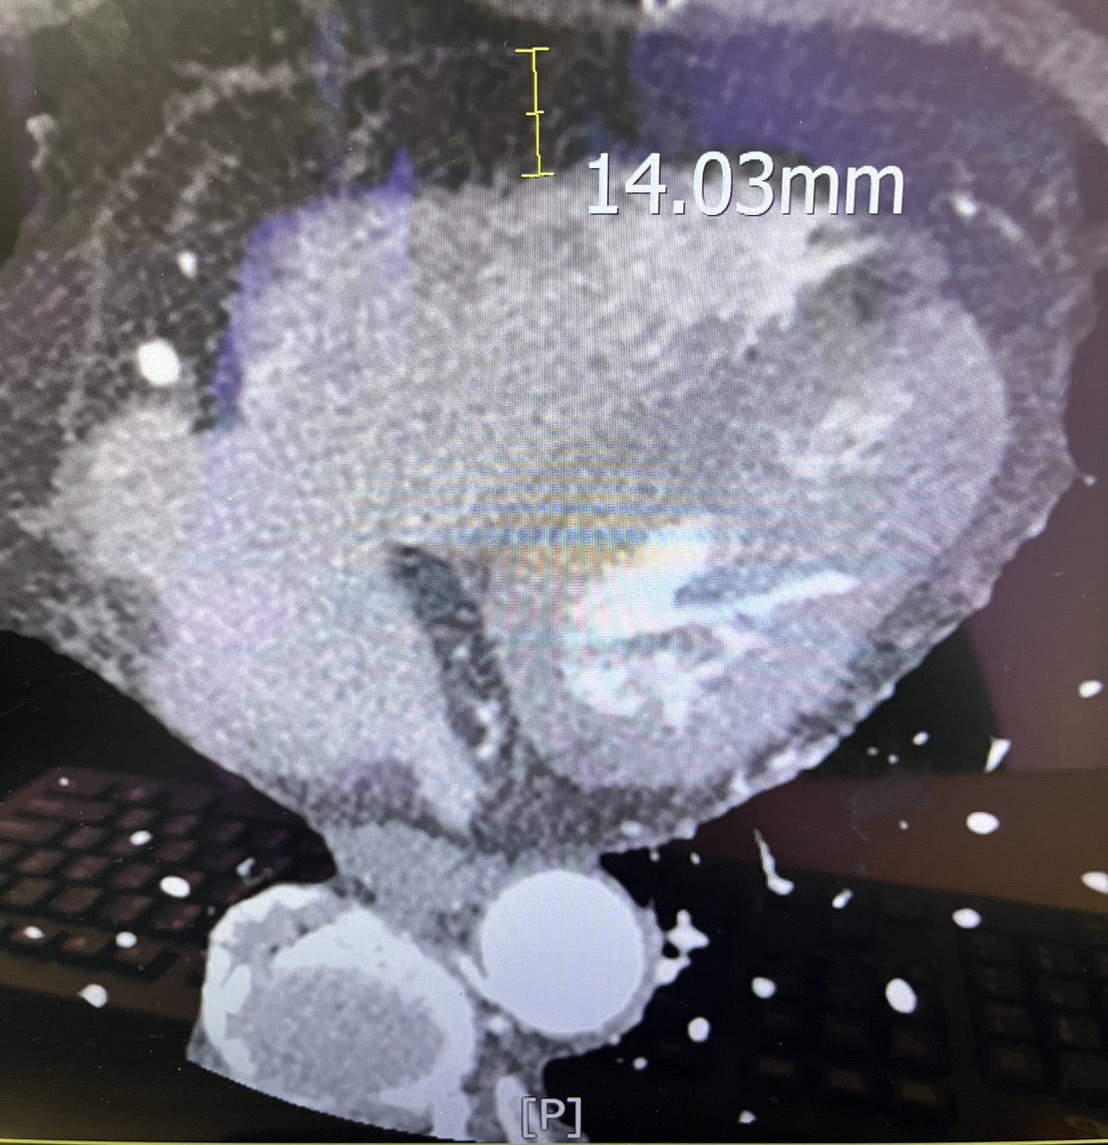

圖:新營醫院家醫科翁靖惠醫師解釋心包膜脂肪

新營醫院家庭醫學科翁靖惠醫師分享,近期一名中年女性BMI-32,求診時表示走路常感氣喘。其心臟電腦斷層顯示心包膜脂肪厚度高達1.4公分(正常約0.4公分),過厚脂肪降低心臟彈性,造成心臟功能受損。